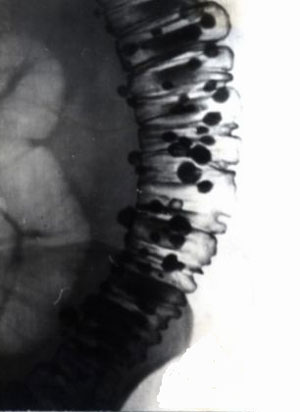

Рис. 3. Стадия полных дивертикулов. Множественные дивертикулы нисходящей кишки.

Предоставил Дементьев Е.З.